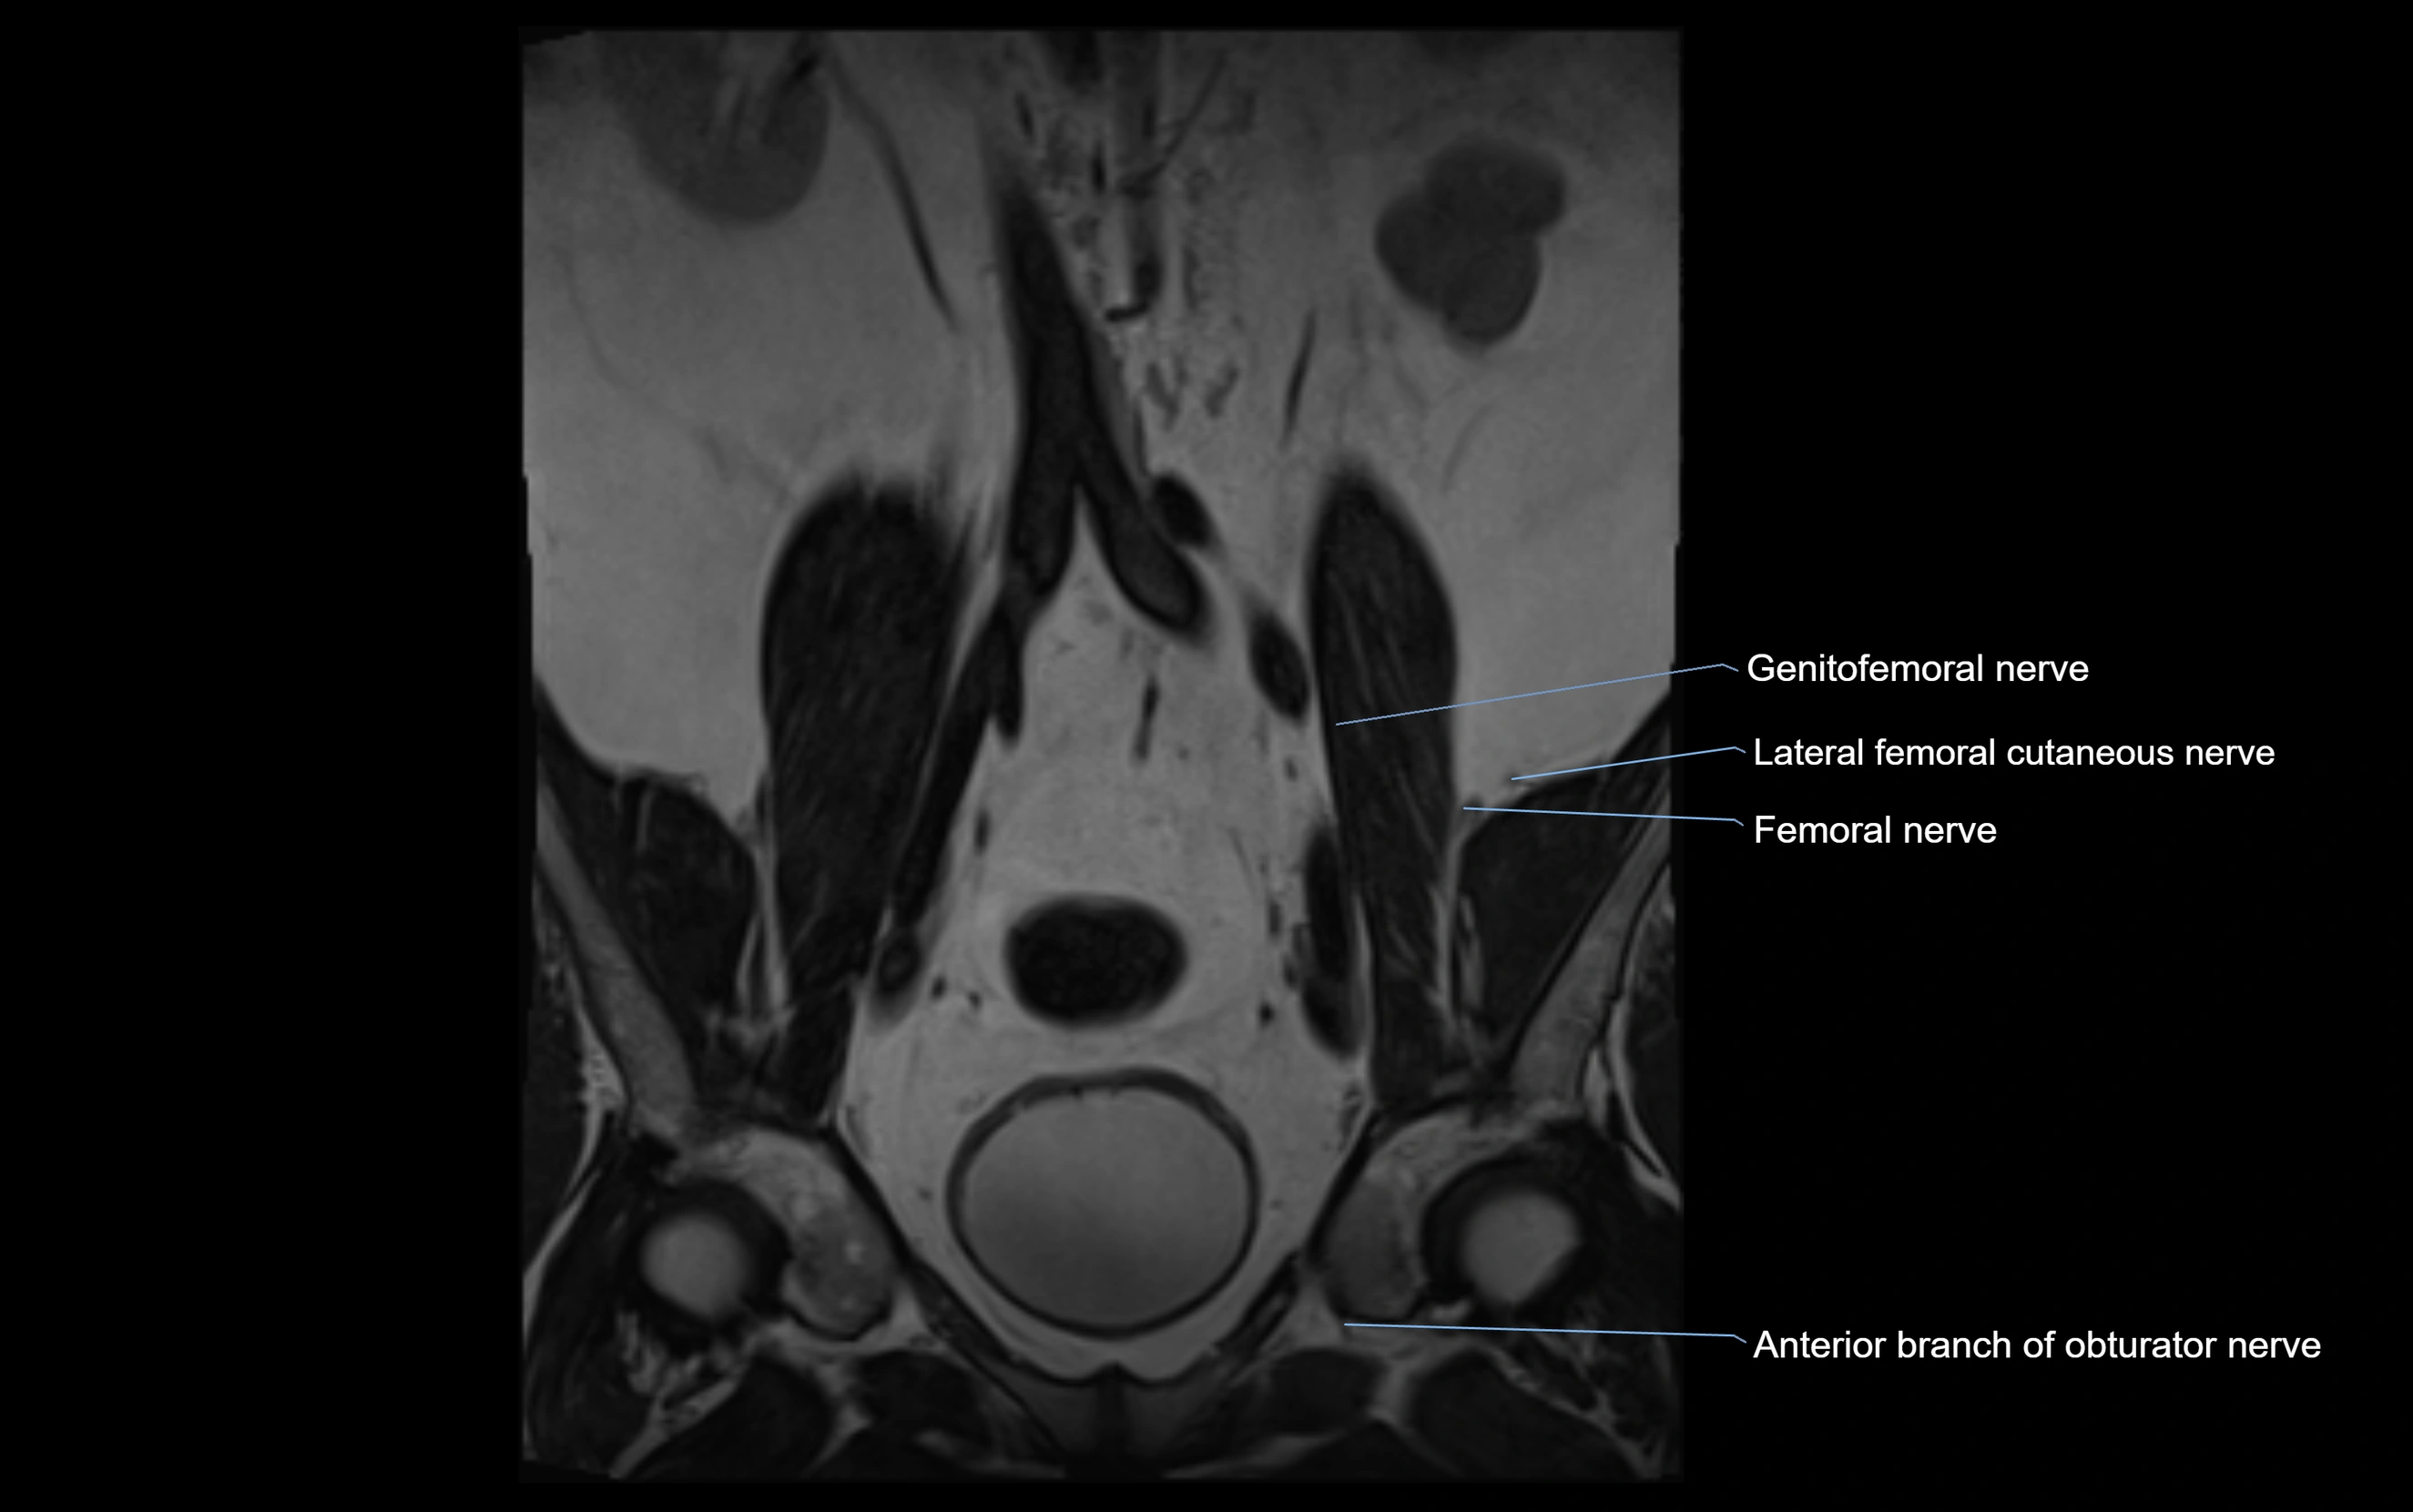

MRI Appearance

T1-weighted images:

• Nerve appears as a very thin low-to-intermediate signal intensity structure

• Surrounded by bright fat, aiding visualization

T2-weighted images:

• Nerve shows intermediate to mildly hyperintense signal compared to muscle

• Pathological involvement appears brighter

STIR (Short Tau Inversion Recovery):

• Normal nerve appears dark

• Inflamed or entrapped nerve appears bright hyperintense

T1 Fat-Sat Post-Contrast:

• Normal nerve enhances minimally

• Pathologic nerve (neuritis, entrapment, tumor infiltration) shows focal or diffuse enhancement

3D T2 SPACE / CISS:

• Nerve appears intermediate to mildly hyperintense compared to muscle

• Surrounded by bright fat or CSF, improving visualization

• Best sequence for mapping small pelvic nerves such as the anococcygeal